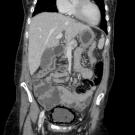

A 61-year-old woman with a medical history of type 1 diabetes on insulin pump, coronary artery disease (CAD) status post–coronary artery bypass graft (CABG), gastroesophageal reflux disease, Hashimoto...

04/10/2024